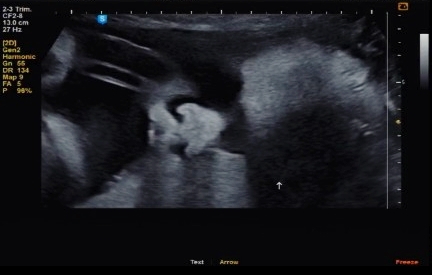

[31주 6일] 정기검진

2주에 한 번씩 정기검진이라 찰떡이 보러 가는 날이 짧아졌다~~ 한 달 기다리는 게 힘들었는데 2주에 한 번...